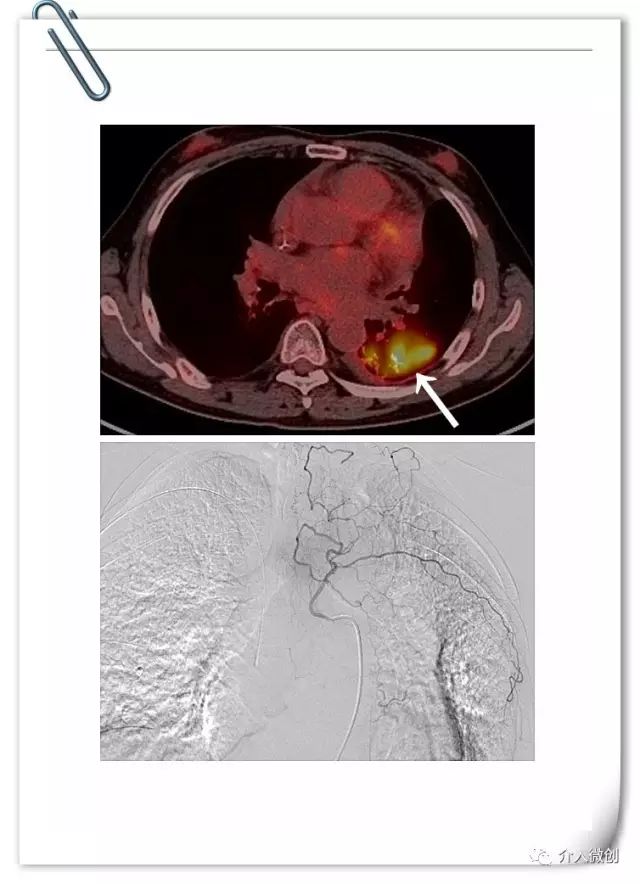

例2:左肺小细胞肺癌放化疗后进展

中年男性患者,左肺小细胞肺癌(局限期),经过EP方案化疗7周期,期间配合同步左肺及纵隔病灶外放疗。治疗后期左下肺病灶持续进展,经调整化疗剂量仍反复出现严重不良反应,无法耐受进一步静脉化疗。

最终患者寻求介入微创治疗,术前PET-CT示左下肺高代谢病灶。DSA下行左支气管动脉化疗灌注术。考虑既往患者多程化疗后出现多次严重骨髓抑制,骨髓造血功能已严重受损,将其化疗剂量降至常规静脉化疗方案剂量的一半!

患者顺利完成2周期动脉灌注化疗,耐受性良好,无明显化疗毒副反应。术后1月后复查CT示左下肺病灶基本消失,术后随访3年余病情一直持续稳定,疗效评价完全缓解。